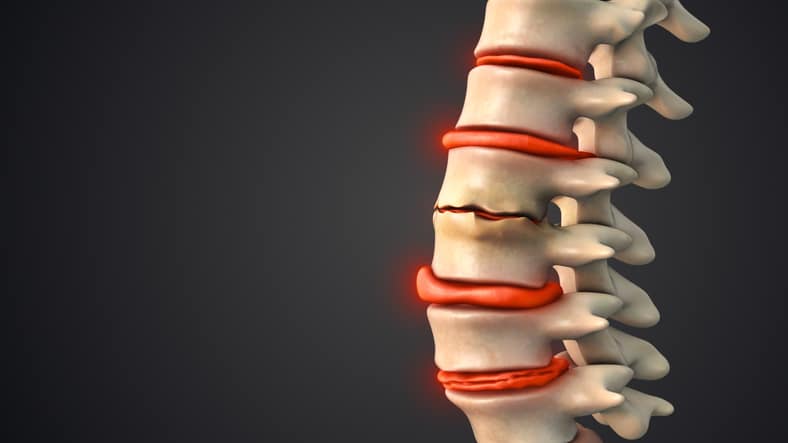

A pinched lumbar nerveย causes debilitating pain and neurological dysfunction. Fortunately, a surgical solution is possible if the source of the pain can be found. NU-Spine: The Minimally Invasive Spine Surgery Institute is a state-of-the-art pain center near you in New Jersey, Florida, and Pennsylvania. We offer a wide range of surgical proceduresย for patients with spine […]